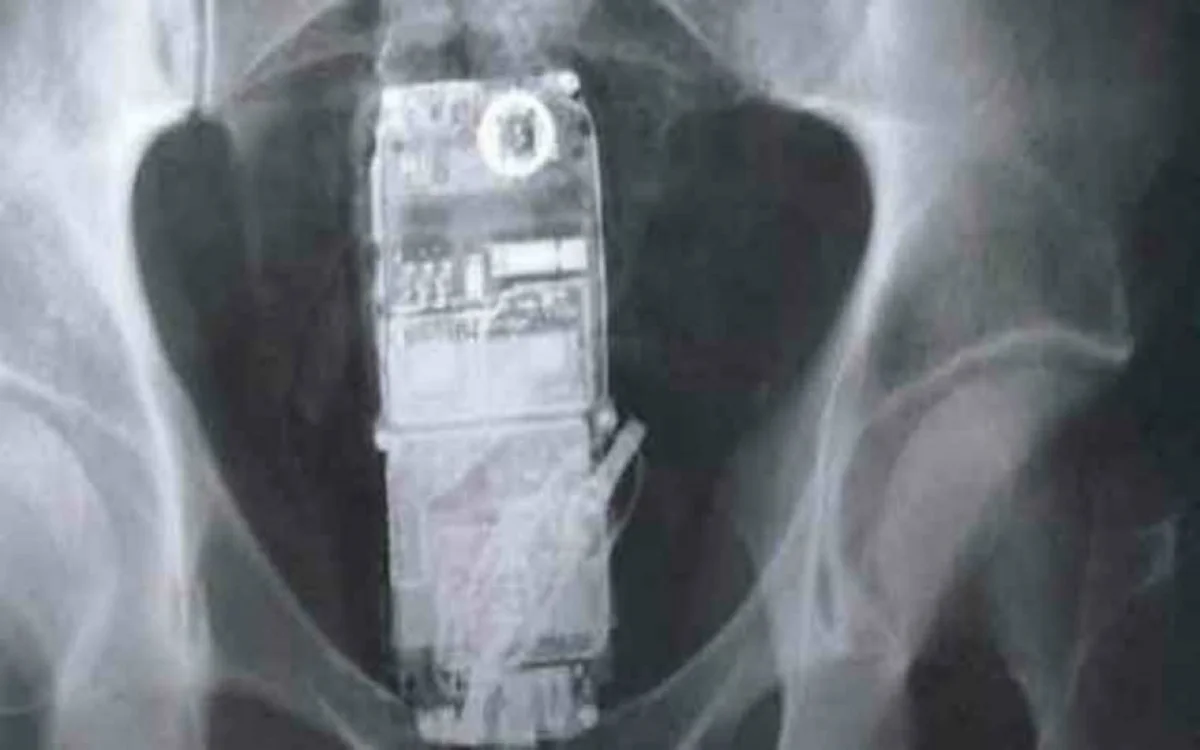

Imagen ilustrativa

De acuerdo a lo que publican diferentes portales, tres presos brasileños fueron descubiertos con 19 teléfonos móviles en sus cuerpos. Uno de ellos tenía 10 celulares en su estómago, según lo informado por fuentes penitenciarias.

La Penitenciaria Silvio Yoshihiko Hinohara, en una ciudad del interior de Sao Paulo, hoy se convierte en noticia porque el sector de inteligencia detecto que tres presos llevaban tanto en el estómago como en el recto aparatos celulares, tras haber pasado por un detector de metales.

Dos de los presos guardaban teléfonos en el recto: uno tenía cuatro micro aparatos y otros cinco; 4 teléfonos de tamaño mayor y un micro celular.

El tercer reo, al pasar por los rayos X descubrieron 10 mini celulares con auriculares en el estómago y debió ser sometido a una operación para retirarle los aparatos.